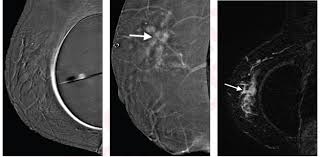

Breast Cancer Screening Accuracy Healthmanagement Org from healthmanagement.org Overall, the sensitivity of mammography is about 87 percent 31 . The earliest a tumor may be found on a mammogram is when it is between 0.2 cm and 0.3 cm in diameter. In females in the uk, breast cancer is the most common cancer, with around 54,700 new cases in 2017. This means mammography correctly identifies about 87 percent of women who truly have breast cancer. Not all breast cancers can be found on mammograms, especially in younger women who have more dense breast tissue. Very early breast cancers are usually easier to treat, may need less treatment, and are more likely to be cured. Mammograms miss about 15 percent of. For women age 40 to 49:

Screening with 3d mammography seemed to find breast cancers at an earlier, more treatable stage in these younger women. After a mammogram that didn't show anything, and a sonogram that found the lump, i was diagnosed with stage 2 breast cancer. Overall, screening mammograms do not find about 1 in 5 breast cancers. Breast cancers found by screening are generally at an early stage. Breast cancers are sometimes detected when very small by the presence of microcalcifications in the breast. Mammography is good at finding breast cancer, especially in women ages 50 and older. The earliest a tumor may be found on a mammogram is when it is between 0.2 cm and 0.3 cm in diameter. Unlike typical breast cancer, ibc usually cannot be detected by a mammogram or ultrasound. Thus, approximately 20% to 28% of breast cancers are interval cancers. Half of women have dense breast tissue, and for those women, mammogram may not be enough. Studies indicate that combining a 3d mammogram with a standard mammogram can result in about one more breast cancer for every 1,000 women screened when compared with standard mammogram alone. Breast cancer is primarily a women's disease, but it does affect men. State that screening reduces breast cancer mortality by 20% or more, because it sounds more impressive than explaining that the absolute risk reduction is 1 in 1,000.

Mammograms May Lead To Breast Cancer Over Diagnosis Study Finds Shots Health News Npr from media.npr.org Little attention has been paid to how interval breast cancers are ultimately discovered. Percent of women aged 40 and over who had a mammogram within the past 2 years: We estimate about 15 percent of breast cancers are diagnosed during a reasonable interval after a negative mammogram. Breast cancers are sometimes detected when very small by the presence of microcalcifications in the breast. The average size of breast cancer, when found on mammograms, is 1.1 cm. Half of women have dense breast tissue, and for those women, mammogram may not be enough. It's so important to listen to the messages our bodies are telling. Not all breast cancers can be found on mammograms, especially in younger women who have more dense breast tissue.

This type of mammogram is called a diagnostic mammogram. Breast cancer is the most common cancer in the uk, accounting for 15% of all new cancer cases (2017). Improve breast cancer detection in dense breast tissue. A breast lump is probably cancer. We estimate about 15 percent of breast cancers are diagnosed during a reasonable interval after a negative mammogram. After a mammogram that didn't show anything, and a sonogram that found the lump, i was diagnosed with stage 2 breast cancer. Screening with 3d mammography seemed to find breast cancers at an earlier, more treatable stage in these younger women. Mammography women diagnosed with breast cancer after having yearly mammograms were diagnosed with cancers that were smaller and less advanced than women who had mammograms every 2 years, according to results from a small study. The current evidence suggests that breast screening reduces the number of deaths from breast cancer by about 1,300 a year in the uk. Luminal a tumors are associated with the most favorable prognosis Little attention has been paid to how interval breast cancers are ultimately discovered. It said 1 million women. The earliest a tumor may be found on a mammogram is when it is between 0.2 cm and 0.3 cm in diameter.